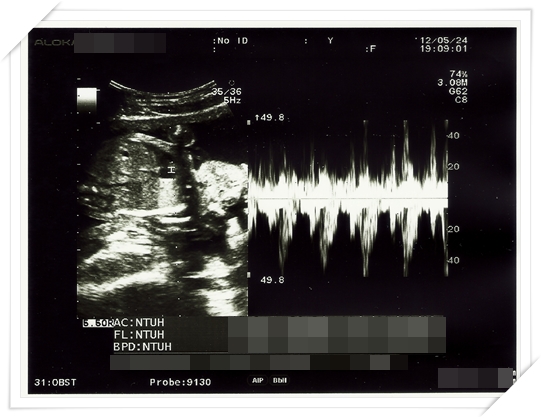

第19週的時候 又來到我們例行產檢的時候啦

照超音波的時候乖的跟甚麼一樣

只有意思意思打打嗝而已

雖然這樣醫生可以很快就順利量到小鴨的大小 頭圍 大腿骨的長度等等

不過事實證明 他長得很好啦~~~ 大小其實都還超前了真正的週數

而且我的週數本來就已經是矯正過後的週數 (依照大小往前推的週數)